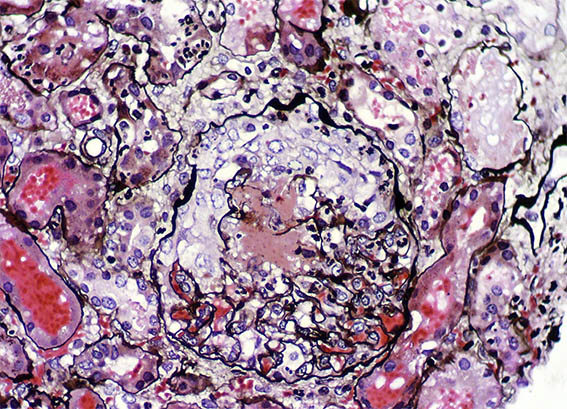

Figure 5. Methenmine-silver stain, X100.

Figure 6. H&E, X200.